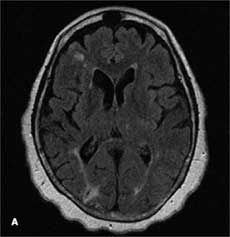

An 81-year-old woman with a history of moderate Alzheimer dementia, depression, coronary artery disease, hypertension, and type 2 diabetes mellitus was accompanied to the office by her son for a routine follow-up appointment.